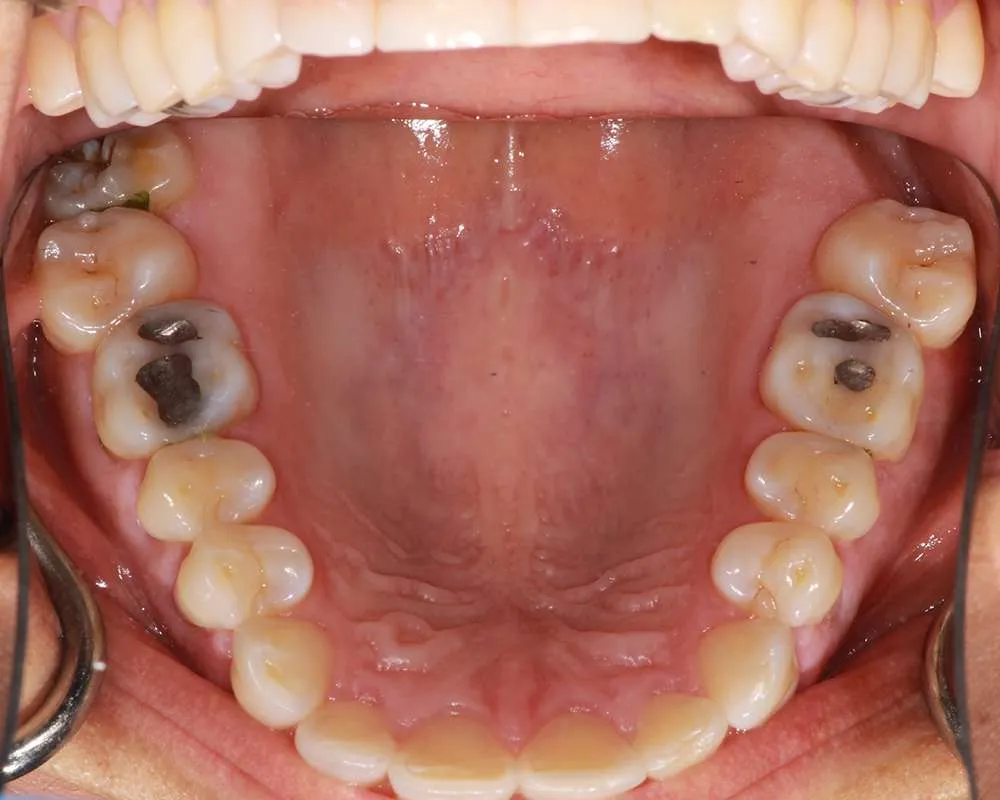

Real Stories, Real Results: Case Studies Showcasing How Our Personalized Approach Transforms Smiles and Lives

Amalgam fillings removed

Witness the Remarkable Changes We Can Achieve